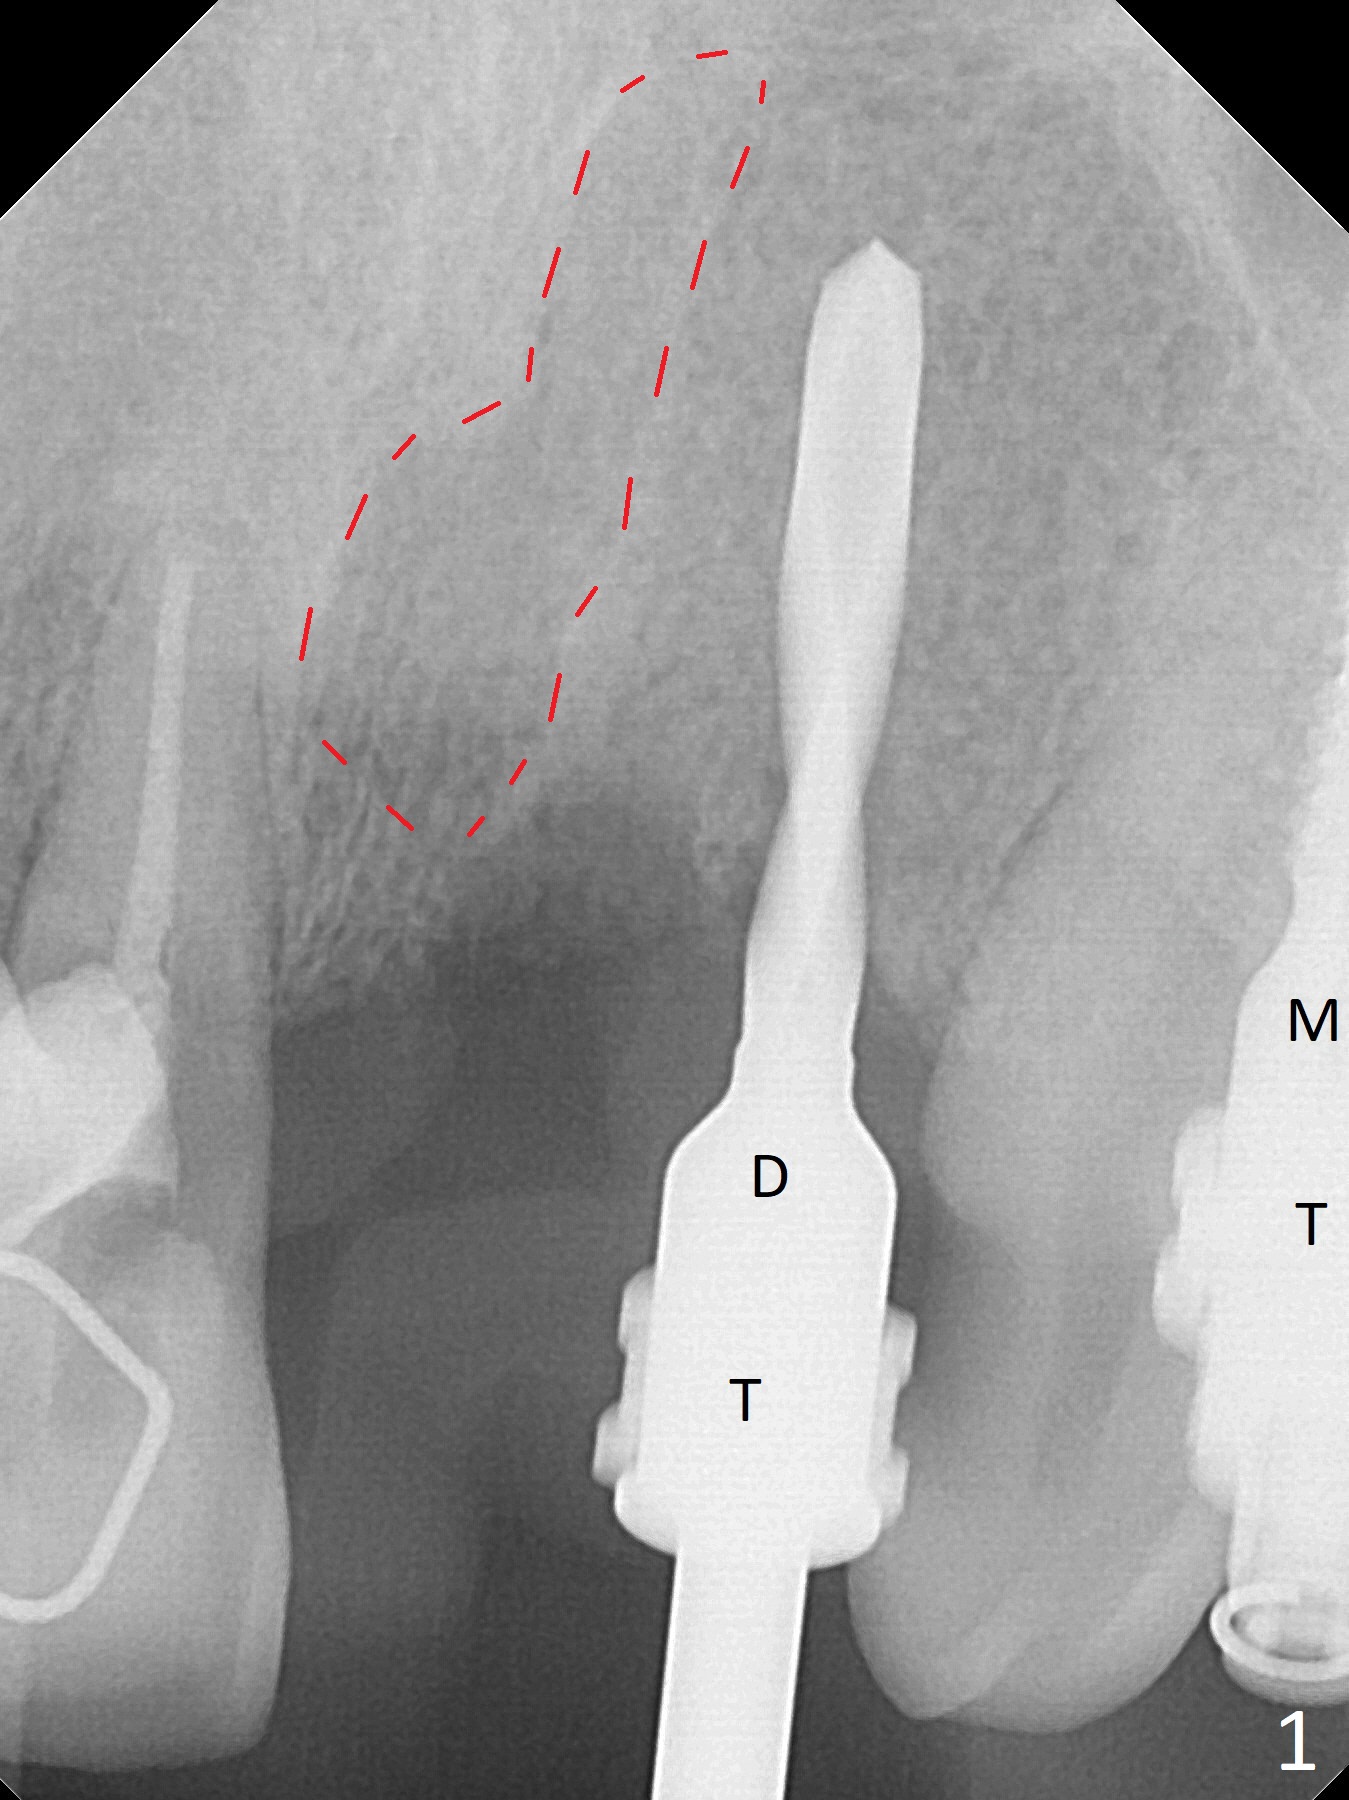

After a 4x10 mm implant is placed with fixture mounting (Fig.2 M) following sinus lift (*) at #12, osteotomy is initiated at #10 (Fig.1 (T: tube of surgical guide)). It appears that the drill (D) has good trajectory (between the Incisive Canal (red dashed line) and the canine root). The final position of the implant at #10 is acceptable (Fig.3). The implant at #12 is placed deeper (Fig.4 (arrow), as compared to Fig.2) because of clinically buccal superficial placement. The most critical challenge is anterior deep bite associated with posterior collapse. Periodontal dressing is applied. When the latter dislodges, there is minimal clearance for a provisional. Periodontal dressing is re-applied. The patient (smoker, partial edentulism with occlusal interference) returns for provisional nearly 1 month postop with chief complaint "something is lost in the back". In fact the healing abutment at #12 is lost with buccal granulation tissue (Fig.5). When a new abutment is seated, there is discomfort. When a healing screw is placed, it cannot be seated completely with two separate trials (Fig.6,7). Should we leave it as it is or open up for complete seating? It appears that the implant is loose. After preparation for clearance at #10, the abutment is retightened. It appears to turn with the underlying implant with discomfort. A 4x5 mm healing abutment is placed to reduce micro-movement. One week later, the infection at #12 dissolves with oral Amoxicillin (Fig.8). Due to limited occlusal clearance and implant tenderness when the abutment abutment is retightened, the cemented abutment is changed to a healing abutment. The implant at #10 seems to be osteointegrated, while the healing screw at #12 remains incomplete seating 3 months postop (Fig.9). The loose healing screw cannot be retightened securely, as there is bone loss around the implant 3 months postop (Fig.10 *). When a 4.5 mm x 15 degree 4 mm cuff angled abutment is placed, the mesiodistal trajectory improves (Fig.11), but there is no occlusal clearance (Fig.12). The latter would form when posterior support is established (Fig.13, either removable appliance (which the patient hates) or fixed one (finance)). Fig.14 shows the unhealed site of #12. Incision confirms the bone loss around the implant, which is removed. Although the sinus floor is absent, there is no membrane perforation. After debridement, allograft mixed with small amount of Osteogen is placed (Fig.15,16 G) and covered with Osteogen plug and 6-month membrane.